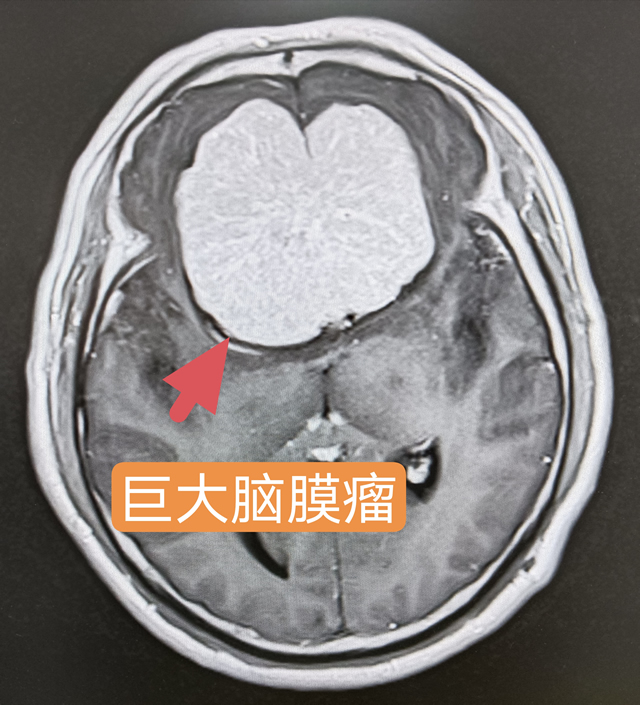

52岁的王先生,自两年前开始头晕头痛,频繁发作的头部胀痛、犯晕让他痛苦不堪。经头颅CT与磁共振检查后,发现其颅内有一枚犹如成年人拳头般大小的肿瘤,还影响到重要神经、血管。如此巨大的肿瘤就像是一颗埋伏在患者脑部的定时"炸弹",随时有可能发生生命危险,手术是唯一有效的治疗方法。